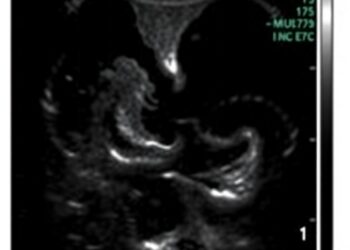

Echocardiographic Markers Predict Risks in Diaphragmatic Hernia

In a groundbreaking advancement within neonatal medicine, researchers have unveiled critical echocardiographic factors that can predict adverse outcomes in infants ...